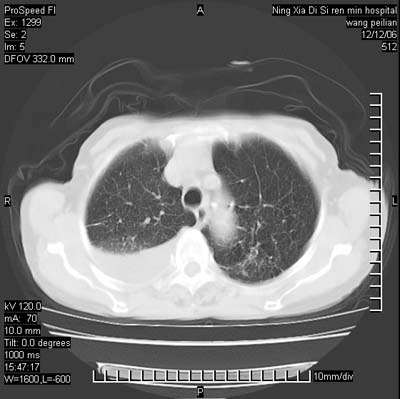

标题: CT5609:胸部:女77 病史不详 [打印本页]

标题: CT5609:胸部:女77 病史不详

两肺可见多个大小不等的结节,左侧有胸水,纵隔淋巴结增大,考虑是细支气管肺泡癌

两肺尖纤维索状影,两下肺结节块状影,且有钙化灶,右胸腔积液。考虑肺结核并胸膜炎。

两肺尖纤维索状影,两下肺结节块状影,且有钙化灶,右胸腔积液。考虑肺结核并胸膜炎肺间质纤维化

两肺以间质性病变为主,并有胸腔积液,考虑结核

考虑:1、慢性支气管炎合并全小叶型肺气肿、间质纤维化;

2、双肺结核;

3、右侧胸膜炎(积液)。

1、双肺继发型肺结核(以纤维、增殖灶为主);

2、右侧胸腔积液;

3、其余符合老年肺改变。

双肺见多个结节状及条索状影,双侧胸腔积液,右侧叶间积液,考虑结核性胸膜炎